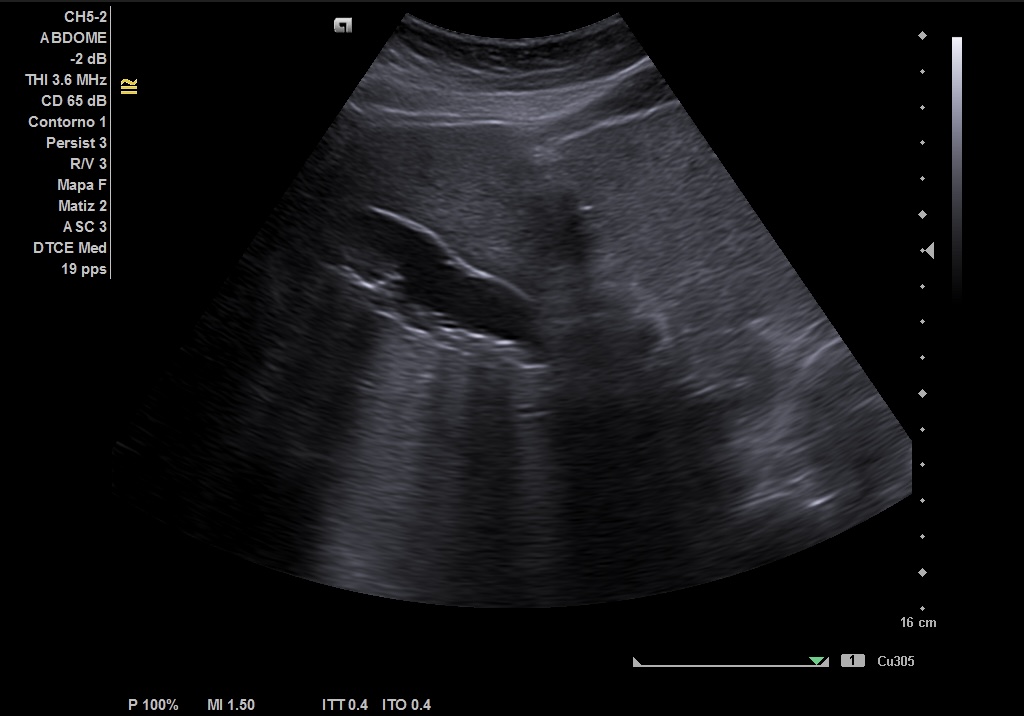

Hallazgos ecográficos

Realizamos ecografía abdominal en el Centro de Salud en el momento de la consulta y visualizamos: Colelitiasis y dilatación de la vía intra y extrashepática sin observar claramente causa obstructiva.

• Nueva ECO de abdomen y colangioRMN en las que se observa: colelitiasis. Vía intra y extrahepática dilatada, sugestivo de coledocolitiasis distal de 5 mm, que se extrae con CPRE.

Pudimos confirmar que se trataba de una ictericia por obstrucción de vía biliar secundaria a litiasis de vesícula, con mismas imágenes encontradas en ECO reglada y en RMN realizadas en centro Hospitalario que las halladas en el Centro de Salud.